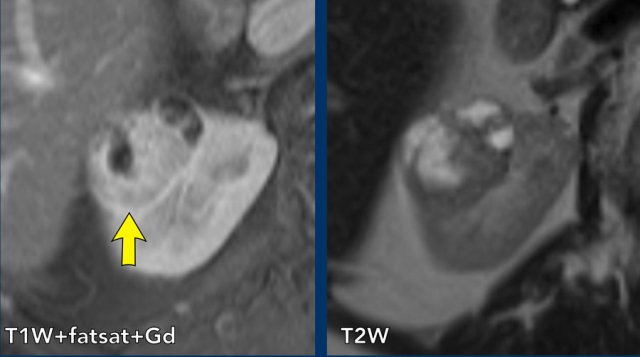

case 2

There is a cystic mass in the right kidney with many (> 4) smooth thin enhancing septa.

The lesion is classified as Bosniak IIF.